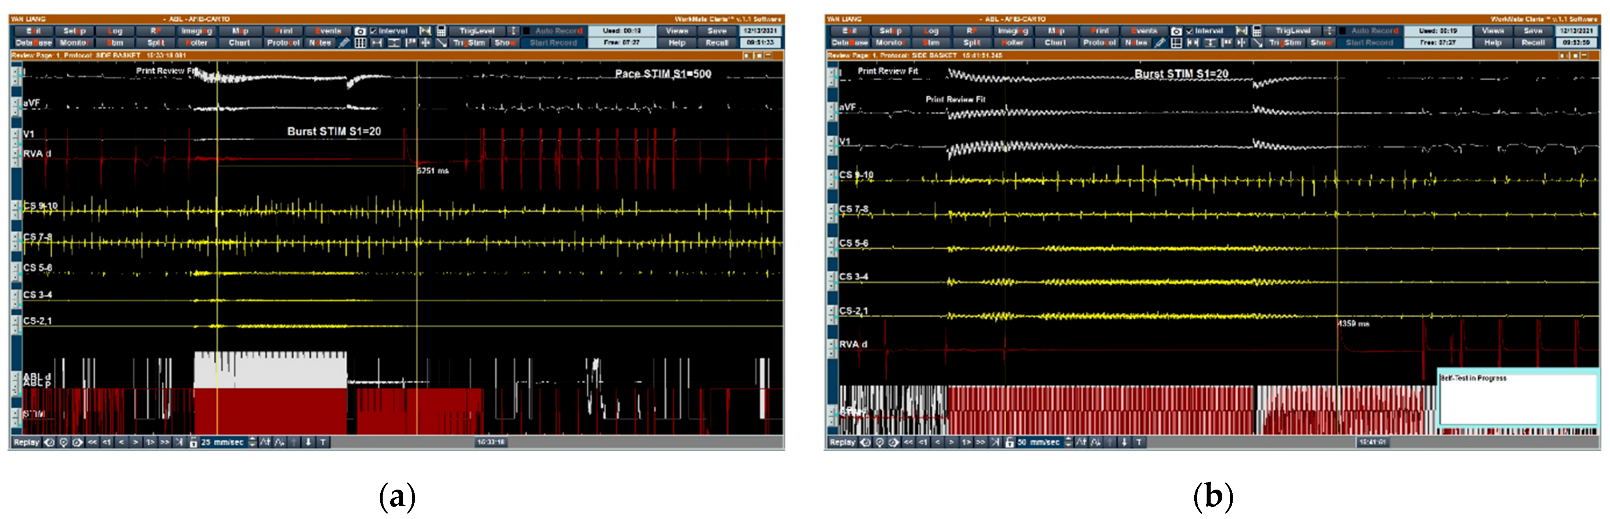

2.4. High-Frequency Stimulation-Guided Endocardial Catheter Ablation of GPs in the LA